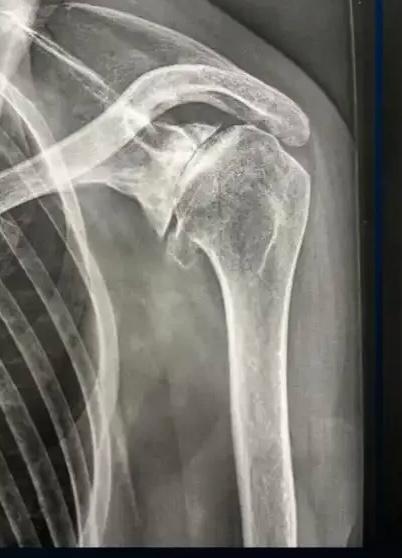

Radiographie d'une arthrose de l'épaule centrée

Radiographie : Arthrose centrée de l'épaule

La radiographie standard : face, profil, rotation interne/externe

Elle va apporter une grande partie des informations nécessaires pour évaluer l'arthrose de l'épaule :

• Pincement de l'interligne articulaire (entre la tête humérale et la glène de l'omoplate)

• Condensation de l'os sous-chondral

• Ostéophytes (inférieur, antérieur, postérieur…) - intérêt +++ des clichés en rotation interne/externe

• Forme de la tête humérale (aplatissement, perte de sphéricité…)

• Géodes, lacunes intra-osseuses

• Centrage de la tête humérale (l'excentration avec surélévation serait en faveur d'une lésion associée de la coiffe des rotateurs)

• Évaluation du stock osseux (surtout sur la glène de l'omoplate)